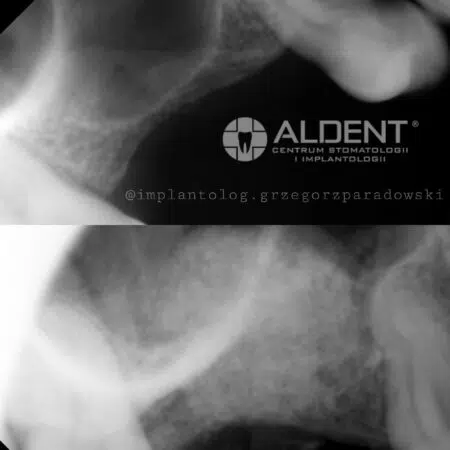

Podnoszenie zatok szczękowych to procedura, która pozwala na zwiększenie objętości tkanki kostnej w zatokach szczękowych, co jest kluczowe dla możliwości przeprowadzenia zabiegów implantologicznych w miejscach o niedostatecznej ilości kości.

- Metoda Otwartego Podnoszenia Zatok

- Metoda ta jest stosowana, gdy konieczne jest znaczące zwiększenie objętości tkanki kostnej. Chirurg wykonuje niewielkie nacięcie w dziąśle, aby uzyskać dostęp do zatoki szczękowej. Następnie delikatnie unosi błonę zatoki i wprowadza materiał kościozastępczy, który stymuluje tworzenie nowej tkanki kostnej.

- Metoda Zamkniętego Podnoszenia Zatok

- Metoda ta jest mniej inwazyjna i jest stosowana, gdy wymagana jest niewielka ilość dodatkowej tkanki kostnej. Materiał kościozastępczy wprowadzany jest przez otwór po ekstrakcji zęba lub przez specjalnie przygotowany otwór w kości.